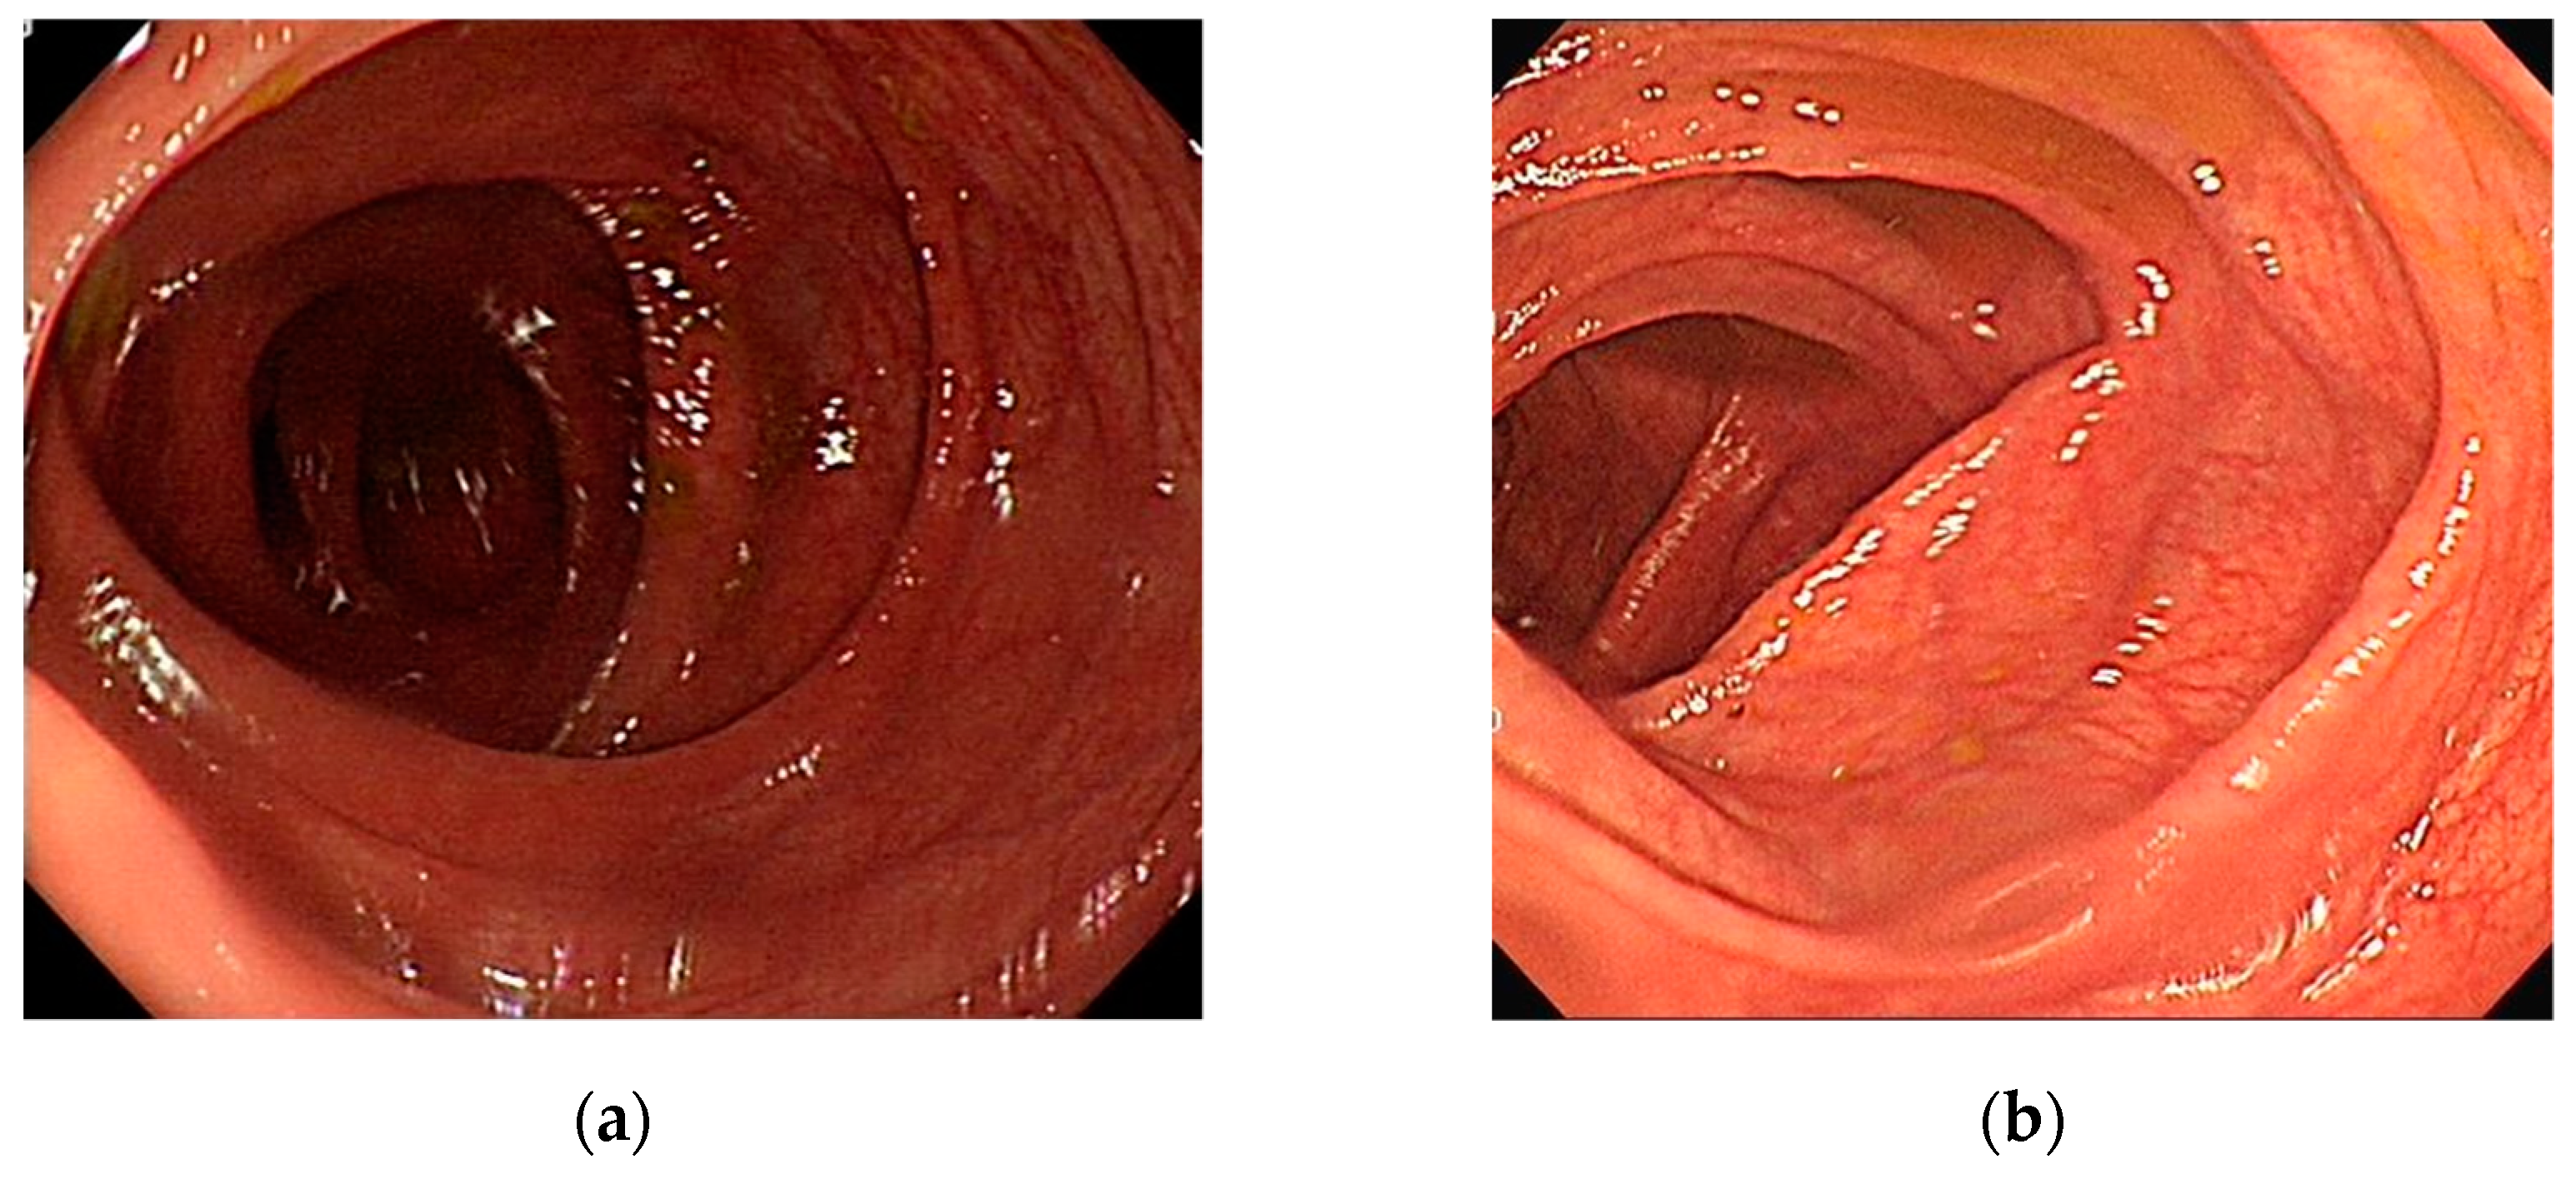

- Polyp (P), if the patient had a polyp or a tumor. If multiple polyps were present, we collected the largest and most prominent textured polyp. The gastroenterologist manually cut the image from central point of the polyp. This also resulted in 181 images. Figure 1a shows one melanosis coli patient’s cecal image and Figure 1b shows the same patient’s cecal image after stopping anthraquinone containing laxative agents for six months.

Figure 1. Melanosis coli patient’s cecal images. (a) The patient took anthraquinone containing laxative medicine one year and his colonoscopy image revealed blackish mucosal pattern in colon. (b) The same patient’s cecal image after six months. Blackish mucosal pattern disappeared after stopping anthraquinone containing laxative agent for 6 months.